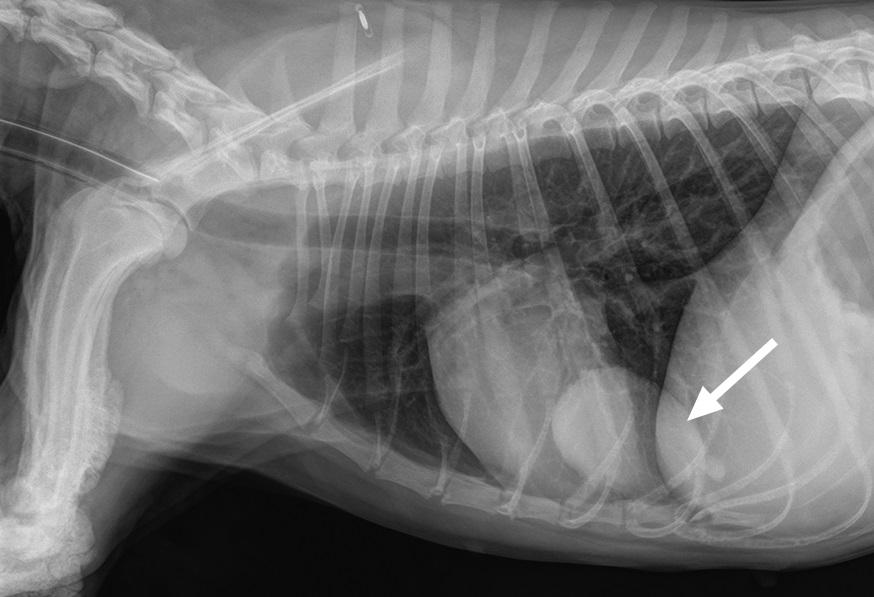

Zur weiteren Diagnostik erfolgte vorerst ein Thoraxröntgen. Es zeigte sich ein weichteildichter Rundherd im kaudalen Lungenfeld. Rat zur Computertomografie zur Evaluation der Operabilität und zum Metastasen-Screening.

Primäre Lungentumoren treten meist beim älteren Hund auf und neigen zur frühen Metastasierung [1] . Klassische Symptome beim Lungentumor sind chronischer unproduktiver Husten und seltener Dyspnoe und Lethargie [2] . Zusätzlich kann es zu einer hypertrophen Osteopathie kommen.

Die hypertrophe Osteopathie ist ein seltenes paraneoplastisches Syndrom, das bei etwa 3% der Hunde auftritt und durch proliferative periostale Reaktionen in den diaphysären Bereichen der Röhrenknochen gekennzeichnet ist [1] , [2] . Eine lokale Hypoxie, Wachstumsfaktoren (VEGF, PDGF) und eine chronische Entzündung werden als Ursache diskutiert [3] . Auch bei nicht tumorösen Veränderungen im Thorax kann es zu einer hypertrophen Osteopathie kommen.

Die Therapie der Wahl stellt eine Lungenlappenresektion mit Biopsie der tracheobronchealen Lymphknoten dar. Eine Chemotherapie (bspw. Vinorelbin) kann bei einer Metastasierung versucht werden. Die hypertrophe Osteopathie bildet sich nach Tumorresektion zurück.